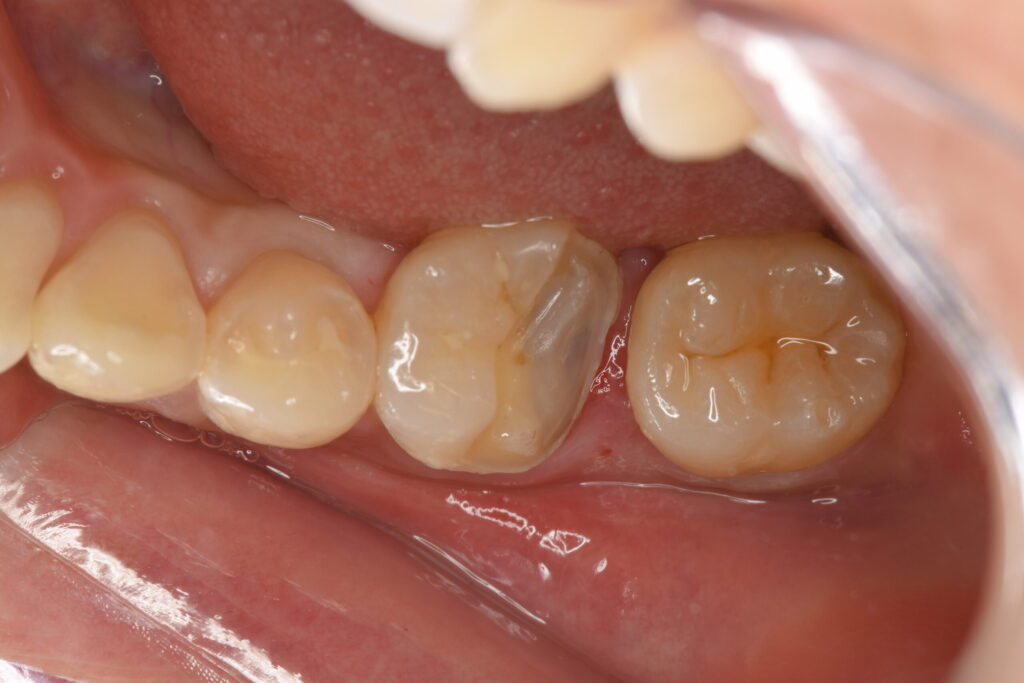

VPT(歯髄温存療法)処置をして1ヶ月後、痛みがなかったためオーバーレイ・テーブルトップベニヤの形成印象を行いました。